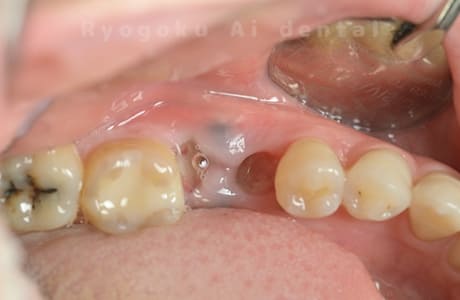

Case11

-

- 原因

- 重度カリエス

- 治療内容

- 自家歯牙移植

- 治療期間

- 約2ヶ月

- 治療費用

- 220,000円

歯が欠けたとのことでご来院された患者様です。虫歯が大きく、保存不可能と判断し、親知らずの移植を行いました。経過良好で、ご本人様も満足されております。

<リスク・副作用>

治療後、痛みや違和感、出血、腫れなどが出る事があります。喫煙者、糖尿病などの方の場合、歯が生着しない場合があります。